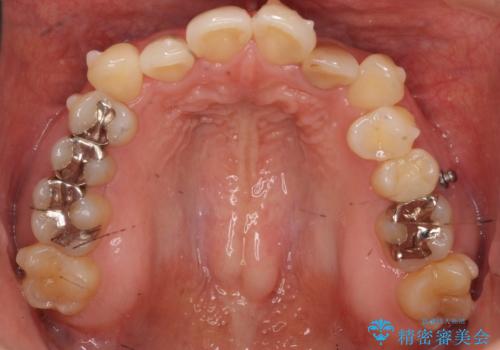

埋まっている奥歯を引っ張り出す インビザライン矯正

- 前歯のがたつきと左下の歯がうまっているとのことで、矯正治療を希望されました。

埋まっている奥歯を並べることで、その後ろの倒れ込んだ歯を整直させることができました。

引っ張り出すことはマウスピース矯正では難しい為、埋まっている歯を並べるスペース確保と、引っ張り出すのに、ワイヤーを用いた部分矯正を行なっています。

上の歯はマウスピース矯正で、奥歯を後ろに下げて、左のかみ合わせのズレを直しています。

上下とも非抜歯で並べています。